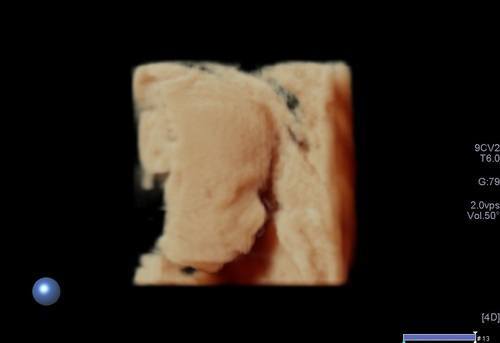

3/4 boyutlu ya da renkli ultrason olarak adlandırılan inceleme ise bebeğin yüzü ya da vücudunun bir kısmının (kollar, bacaklar, eller,ayaklar gibi ) görüntülenmesi anlamına gelir. Bu incelemenin tanısal bir katkısı olmamakta olup daha çok anne, baba ve yakınları için hatıra için yapılmaktadır.